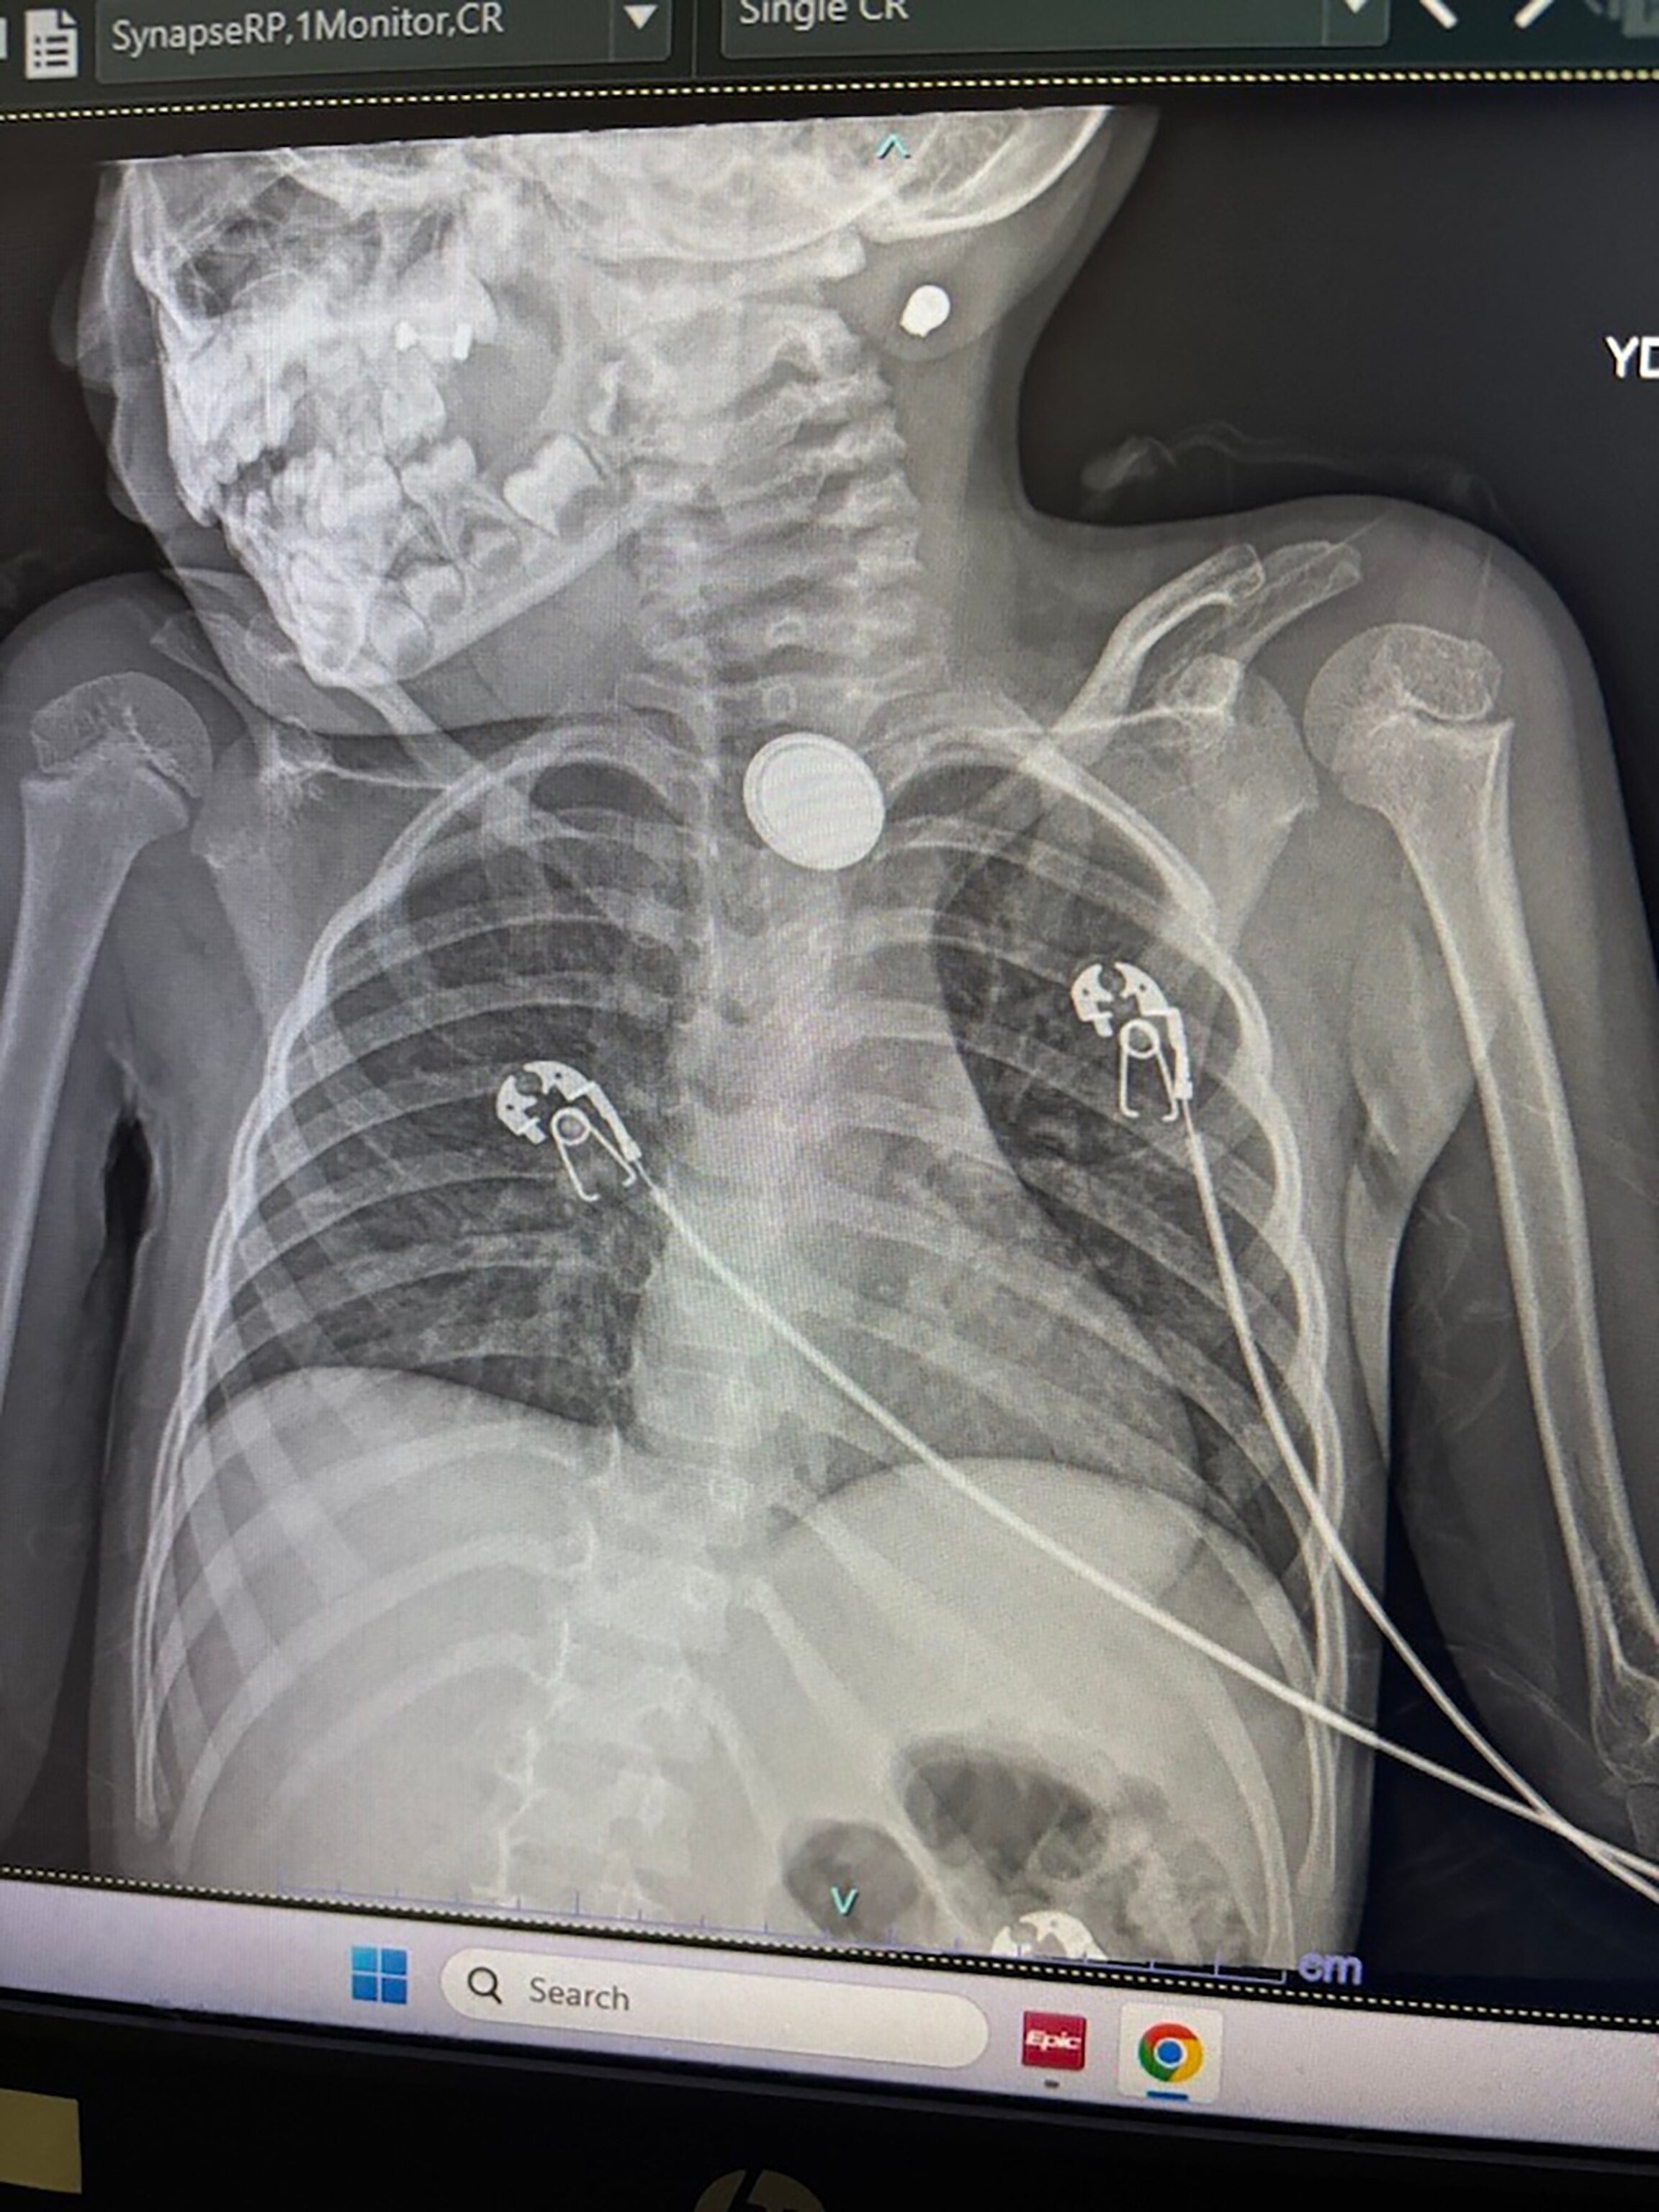

“They did an X-ray and they said, ‘Hey, we need to transport you to Children's Hospital in Aurora because we don't specialize in this. This can be a very dangerous situation,” Sandoval recounted.

At Children’s Hospital Colorado, doctors diagnosed Elana with a foreign body (button battery) ingestion.

Dr. Edwin de Zoeten, director of the Pediatric Inflammatory Bowel Disease Center at Children's Hospital Colorado, told ABC News doctors were able to remove the button battery from inside Elana’s body but the battery caused a perforation in Elana’s esophagus, which led to mediastinitis, or inflammation and subsequent infection of the mediastinum, the space in the chest between the lungs that contains tissues and organs of the chest.

Elana also needed a feeding tube, antibiotics and is under observation for a risk of further injury or complications.

“Her prognosis is guarded as button batteries can cause continued expansion of inflammation and burn even after the battery is removed,” de Zoeten explained via email. “This can lead to a bleed in larger vessels for up to 20-30 days after the battery is removed. If everything heals well, she may need endoscopic treatment to dilate the esophagus due to development of strictures at the site that the battery was found in the esophagus.”